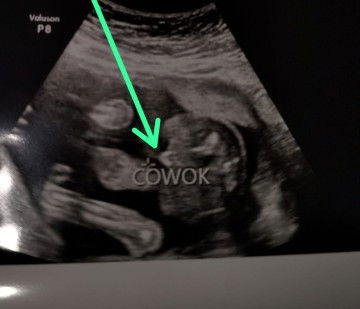

USG 20 week

Bun mau tanya cara baca JK?ini Beneran cowok apa bisa berubah bun.makasih

semua bisa berubah Bun, aku USG bilangnya cewe, yg lahir cowo. untung aku nyiapin peralatan yg warnanya netral. sodaraku malah sebelum sesar di USG cowo, lahirnya cewe.